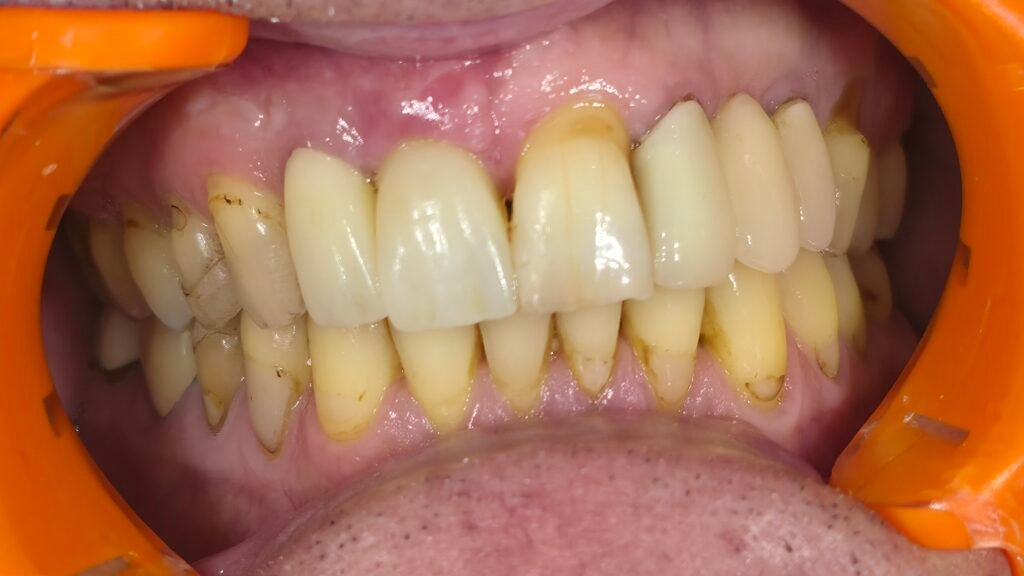

Réhabilitation complète avec mise en charge immédiate (4 implants bas / 6 implants haut)

Le patient se présente avec des dents qui bougent, en haut et en bas.

Nous avons commencé par la mâchoire inférieure avec 4 implants et une mise en charge immédiate.

Trois mois après, le haut a été fait avec le même principe avec 6 implants.

Cette fois-ci, il existait un déficit osseux, résolu par une technique d’expansion sans avoir recours à la greffe d’os.

Les prothèses réalisées sont vissées, ce qui permet de les enlever, les nettoyer une fois par an, ou résoudre n’importe quel problème.